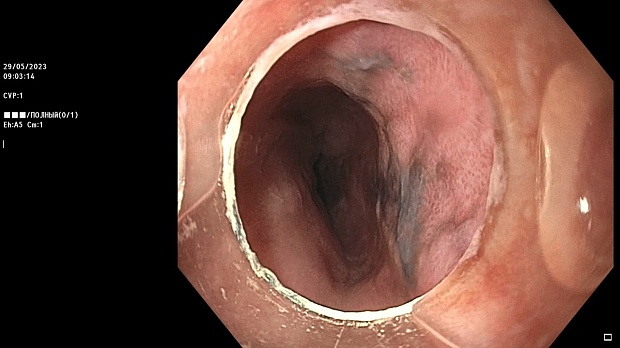

Иллюстрация №2: Эндофото. Сидероз нижней трети пищевода, осмотр в белом свете в близкофокусном режиме

Согласно полученным данным - в среднегрудном и нижнегрудном отделах пищевода определялась проксимальная граница плоских неправильной формы поверхностных рубцов суммарной протяженностью до 8,0 см. На этом фоне в зонах поверхностных рубцов по задней полуокружности визуализировались участки гиперпигментации в темный цвет (Рис. 1). При исследовании в режиме Dual Focus было отмечено наличие мелких (до 0,001 см) черно-коричневых включений, расположенных субэпителиально - в строме слизистой оболочки, сливания их в единый конгломерат не определялось (Рис. 2). При эндосонографии с применением минидатчика с частотой сканирования 20МГц выявлено, что все слои стенки четко дифференцируются, не утолщены, в слизистой оболочки визуализированы мелких гиперэхогенные включения с эхотенями (Рис. 3).

Протокол ЭГДС

В пищеводе в шейном его отделе на уровне 16 см от резцов циркулярно визуализированы единичные синюшные флебоэктазии размерами до 0.5 см. Дистальнее пищевод визуально не изменен до уровня 28 см от резцов, где определяется проксимальная граница плоских неправильной формы поверхностных рубцов, распространяющихся до уровня 36 см от резцов. На этом фоне в зонах поверхностных рубцов по задней полуокружности визуализированы участки гиперпигментации в черно-коричнеый цвет. При осмотре в режиме Near Focus с увеличением - между зон пигментации определяются расширенные капилляры типа II по Inoue-классификации. При биопсии отмечена десквамация плоского эпителия, визуализированы мелкие черно-коричневые включения в строме слизистой оболочки, размеры их до 0,001 см, сливания их в единый конгломерат не отмечается. При эндосонографии с датчиком 20Мгц в исследуемой зоне в слизистой оболочке определяются гиперэхогенные включения, в то время как в подслизистом слое - зоны со сниженной эхогенностью. При биопсии отмечается уплотнение ткани, однако истинной фрагментации не определяется. Уровень Z-линии совпадает с уровнем анатомического кардиоэзофагеального перехода. Розетка кардии эластичная, смыкается не полностью, расположена на уровне пищеводного отверстия диафрагмы.